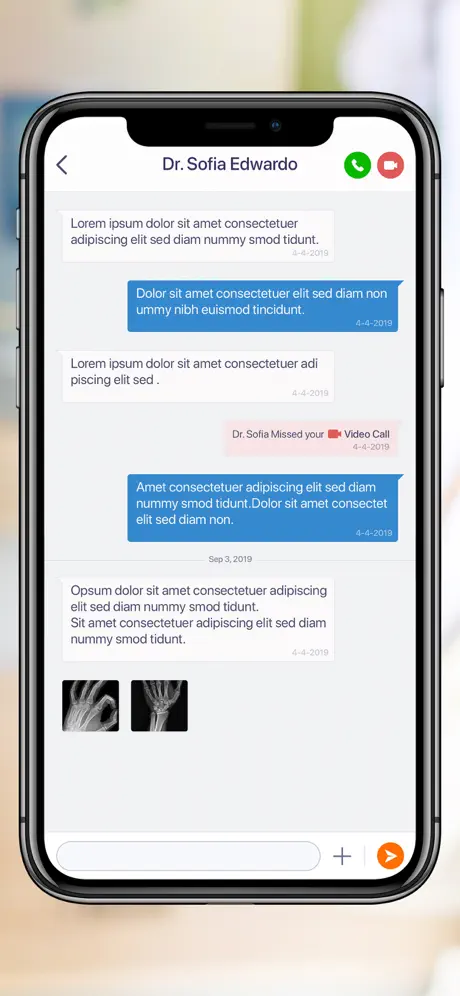

- Ver la información de contacto de sus proveedores de cuidado y comunicarse con ellos a través de mensajería segura

- Conectar y compartir los estudios radiológicos de forma segura con sus proveedores de atención

- Ver la información de contacto de sus proveedores de cuidado y comunicarse con ellos a través de mensajería segura

- Conectar y compartir los estudios radiológicos de forma segura con sus proveedores de atención